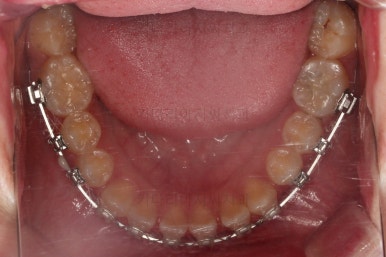

동래교정치과 초진 시 입안의 모습입니다.

치아가 벌어진 것도 벌어진 것이지만 교합이 전혀 안되고 있었어요.

틈새도 아랫니에 훨씬 많았고요.

윗니가 있는 위턱뼈가 전반적으로 아래턱에 비해 3차원으로 작은 양상이었습니다.

이번 환자분은 아랫니가 전반적으로 앞이든, 뒤든, 양옆으로든 넓어져 있는 양상이었고 그래서 아랫니에 틈도 많고 아래 앞니도 밀려나와 있는 양상인거죠.

동래교정치과 첫 단계로 악궁확장 장치를 했습니다.

위턱과 아래턱의 폭이 맞지 않을 때 위턱을 넓혀주는 것이 악궁확장인데요.

그러면 어쩔 수 없이 틈새가 있어도 넓은 아래턱과 조화가 맞게 위턱을 더 넓힐 수 밖에 없습니다.